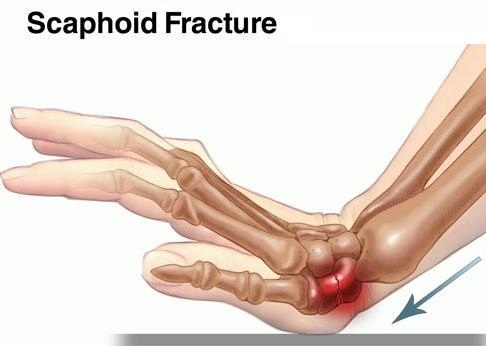

- 주상골 골절은 손목뼈에서 가장 흔하게 골절되고 특히 젊은 남자에서 골절이 많습니다. 특히 자전거나 오토바이를 타거나 축구 등의 운동 시에 넘어지면서 손을 뻗다가 많이 발생합니다.

- 주로 넘어질 때 팔꿈치를 뻗으면서 손목을 뒤로 젖힌 상태로 바닥에 짚은 경우(신전, 수배굴곡)에 손목 관절의 8개의 뼈 중 주상골의 골절이 흔히 일어납니다.